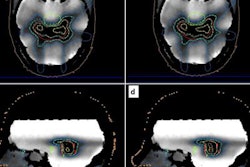

The debate speakers (left to right): Daniela Thorwarth, PhD; Ludvig Muren, PhD; Ben Heijmen, PhD; Julian Malicki, PhD; and Giovanna Gagliardi, PhD.But imaging plays an integral role in all areas of radiotherapy, Thorwarth emphasized. CT is used for treatment planning, dose calculation, and target delineation; images are used for patient positioning, tumor staging, response monitoring, functional characterization, plan adaptation, and proton range verification; the list goes on.

And the future has already started, Thorwarth added, citing the emergence of MRI-guided radiotherapy, which enables daily online guidance. Quantitative imaging, using PET/MR imaging, for example, will enable further personalization of radiotherapy dose prescriptions. This will require additional training and "dedicated QA procedures that may take us out of our comfort zone," she noted.

One example is the use of deep-learning algorithms for automated image delineation, an emerging application that could save clinicians time during treatment planning. "The ability to automate in a reliable way will have a big impact," said Heijmen. Elsewhere, statistical modeling could be used to verify treatment plans, and virtual SPECT/CT scans could be generated for functional avoidance-based planning. "Complex computation is responsible for major breakthroughs and will increasingly do so," he added.